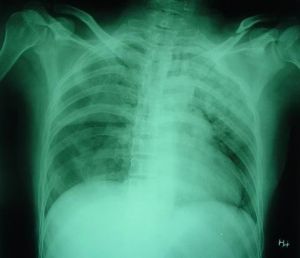

嚴重的閉合性胸部損傷導致多根、多處肋骨骨折,使局部胸壁失去肋骨支撐而軟化,並出現反常呼吸:吸氣時軟化區胸壁內陷,呼氣時外突稱為連枷胸。然而,如果軟化胸壁面積比較大,一般一側在5根及以上肋骨骨折時,甚或雙側累計大部分肋骨,此時,患者大多需要人工或者機械輔助呼吸,出現被動呼吸:吸氣時軟化區胸壁外突,呼氣時軟化區內陷,如果沒有輔助呼吸,大多患者很快陷入窒息而死亡,此種外傷應該與連枷胸區別開來,稱作“胸廓碎裂傷”。

由於常合併有肺挫傷、肝、腎、腦等複合外傷、誘發急性呼吸窘迫綜合徵(ARDS)或者多器官功能衰竭等導致危急臨床病症,使得治療困難甚至死亡,而且死亡率